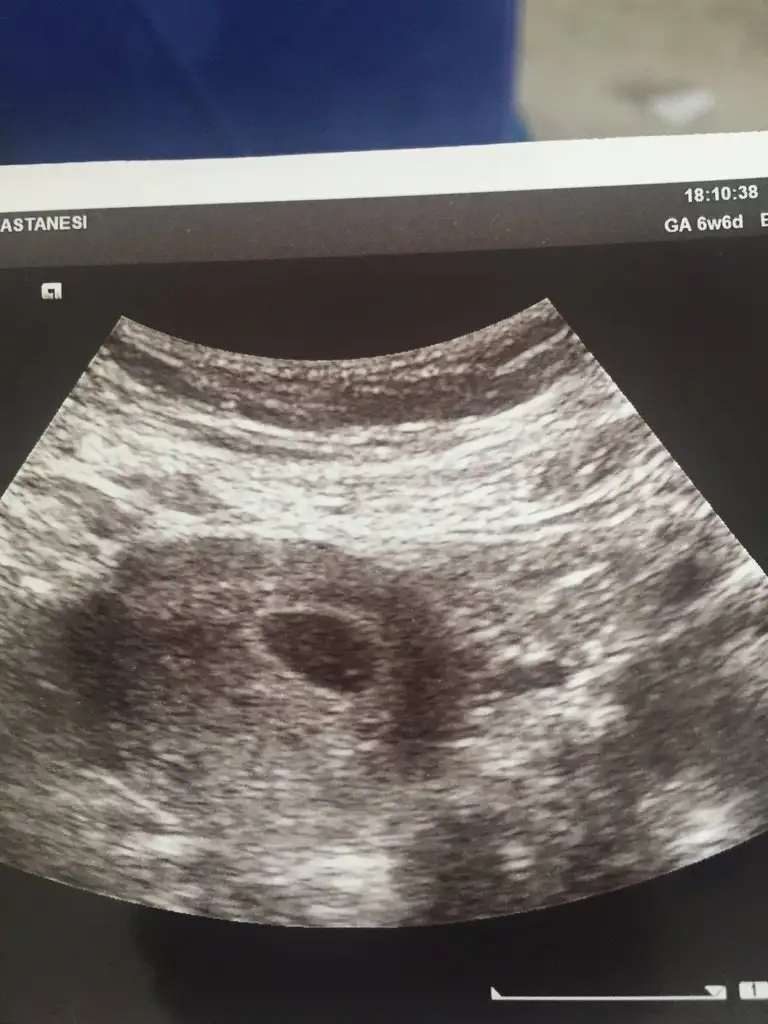

Pikolata banada plesentadan yorum yaparmisin cok rica etsem ilki 7 ikincisi 9 haftalik 2 side karindan usg6 veya 7 haftalık ultrason görüntüsü lazım. bir de karından mı yoksa vajinal mi ultrasonun belirtirsen sana da tahmin de bulunuruz.

Bu teoriye gore bebegin konumu onemli degil..plesentanin hangi tarafta oldugu onemli..plesenta nispeten daha parlak duruyo ultrason kagidinda ama bunu tespit etmek zor..

Hala buralardaysan canim banada plasentaya gore yorum yaparmisin 7 hafta ilki digeri 9 Hafta ikiside karindanKız cnm plasentayi net gördüm ama teori bu tabi tutar tutmaz